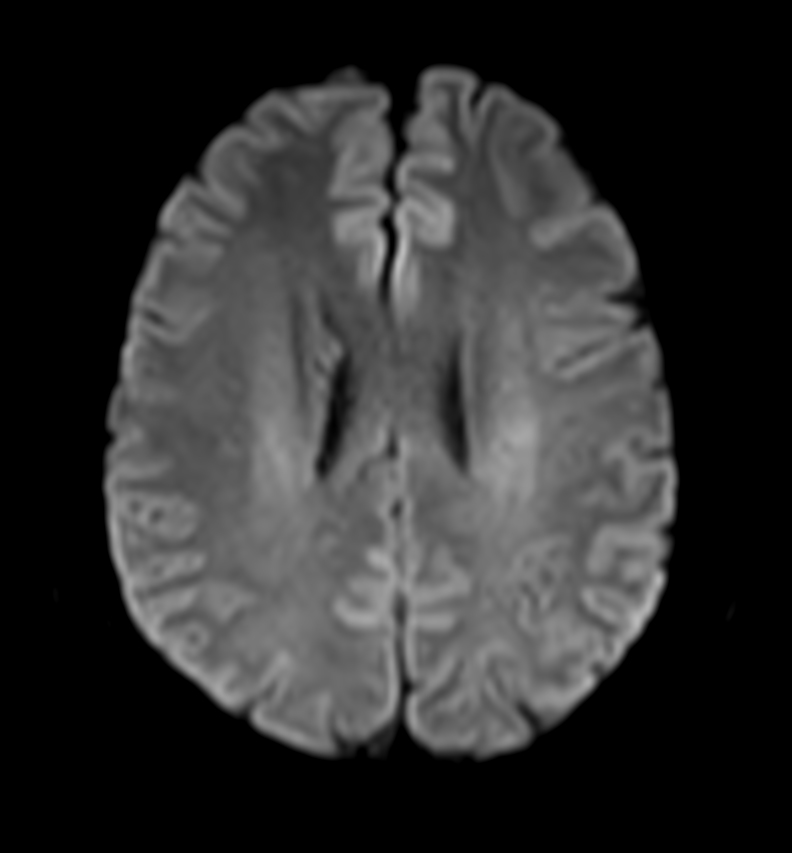

Axial DWI (b1000)